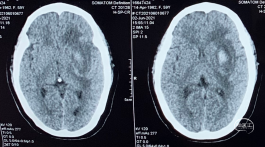

术前DSA 3D:左颈内动脉正侧位及工作位,前交通动脉瘤,约4×8mm,颈宽约6.5mm,形态宽颈、分叶。前交通动脉及大脑前动脉A1、A2直径约2mm。

术前DSA:LICA正侧位及工作角度造影显示前交通动脉瘤

术前DSA:RCCA正侧位造影